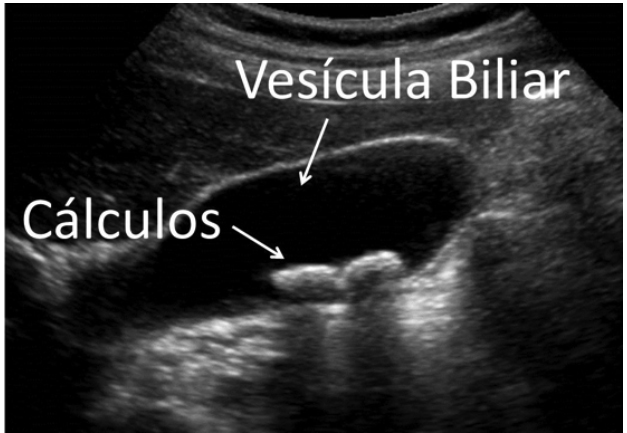

Pedras na Vesícula

Pedras na vesícula, quando tratá-las?

Entenda os sintomas, riscos e o momento certo para buscar tratamento cirúrgico para os cálculos biliares.